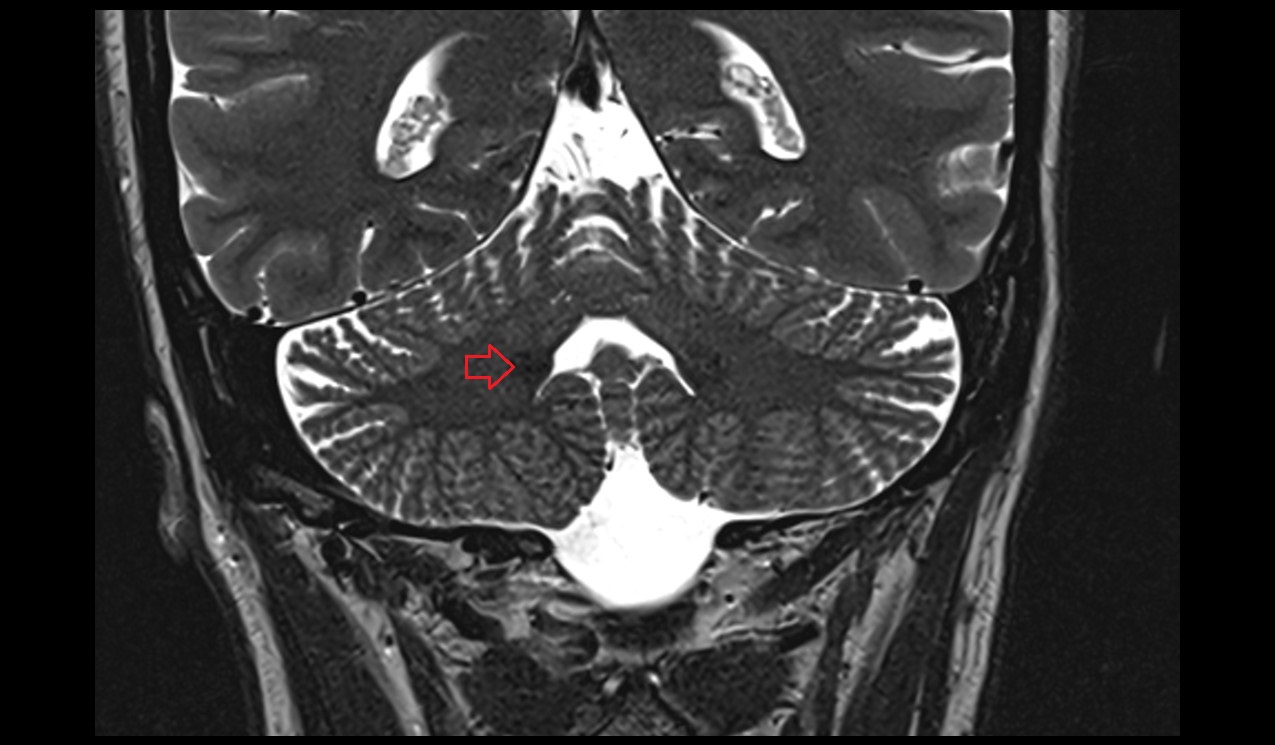

- Cerebellum

- Crus I of ansiform lobule of cerebellum

- Crus II of ansiform lobule of cerebellum

- Paramedian lobule (HVII) of cerebellum

- Simple lobule (HVI) of cerebellum

- Biventral lobule (HVIII) of cerebellum

- Cerebellar tonsil (H IX)

- Posterior inferior cerebellar artery